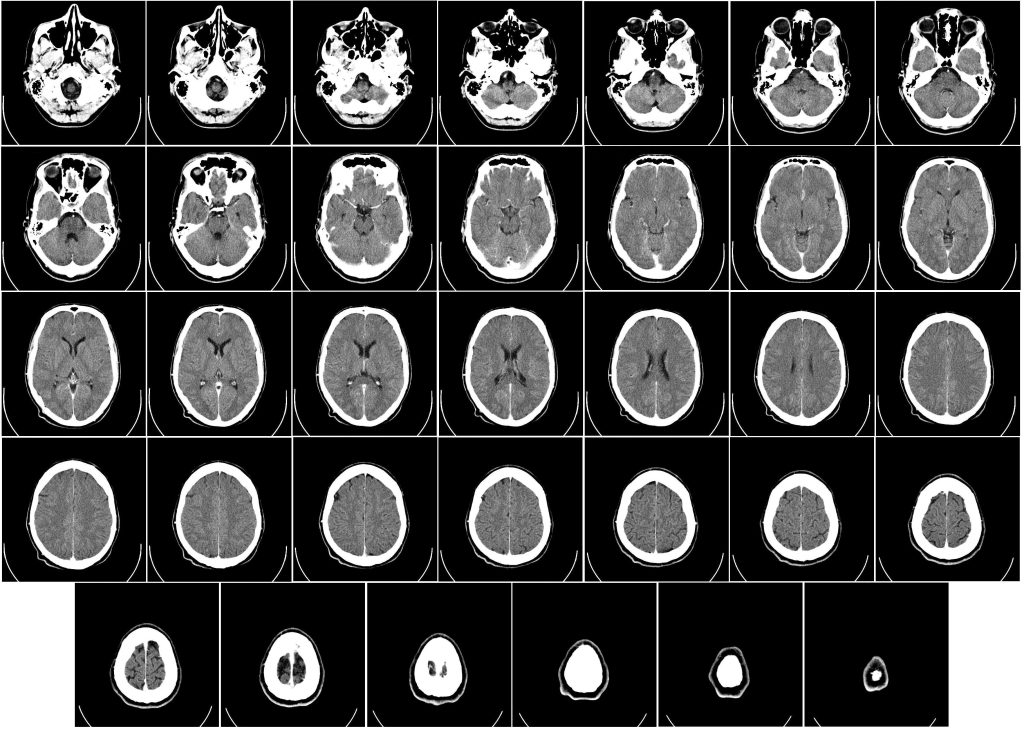

While working as a security guard at the Golden Nugget Casino, Katina Hodges fainted and fell to the floor. Her legs and knee hit the floor. She hit her head on the floor and appeared to have seizures. At Christus St. Patrick Hospital in Lake Charles, Louisiana, a CT scan showed she suffered a hemorrhage in her brain. Hodges subsequently received treatment for her injuries, which included aggravations of preexisting conditions.